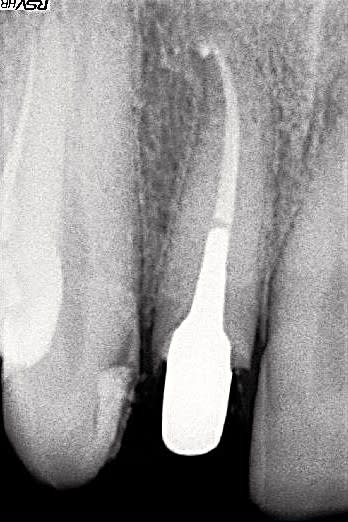

suite de la démo avec le passage d'une lésion que l'on pourrait qualifier de 4 (voire 3 si on compare avec ce que nous donne comme exemple les auteurs dans leur article) sur la radio initiale en une lésion de type 2 (en cours de cicatrisation) 3 mois après le retraitement.